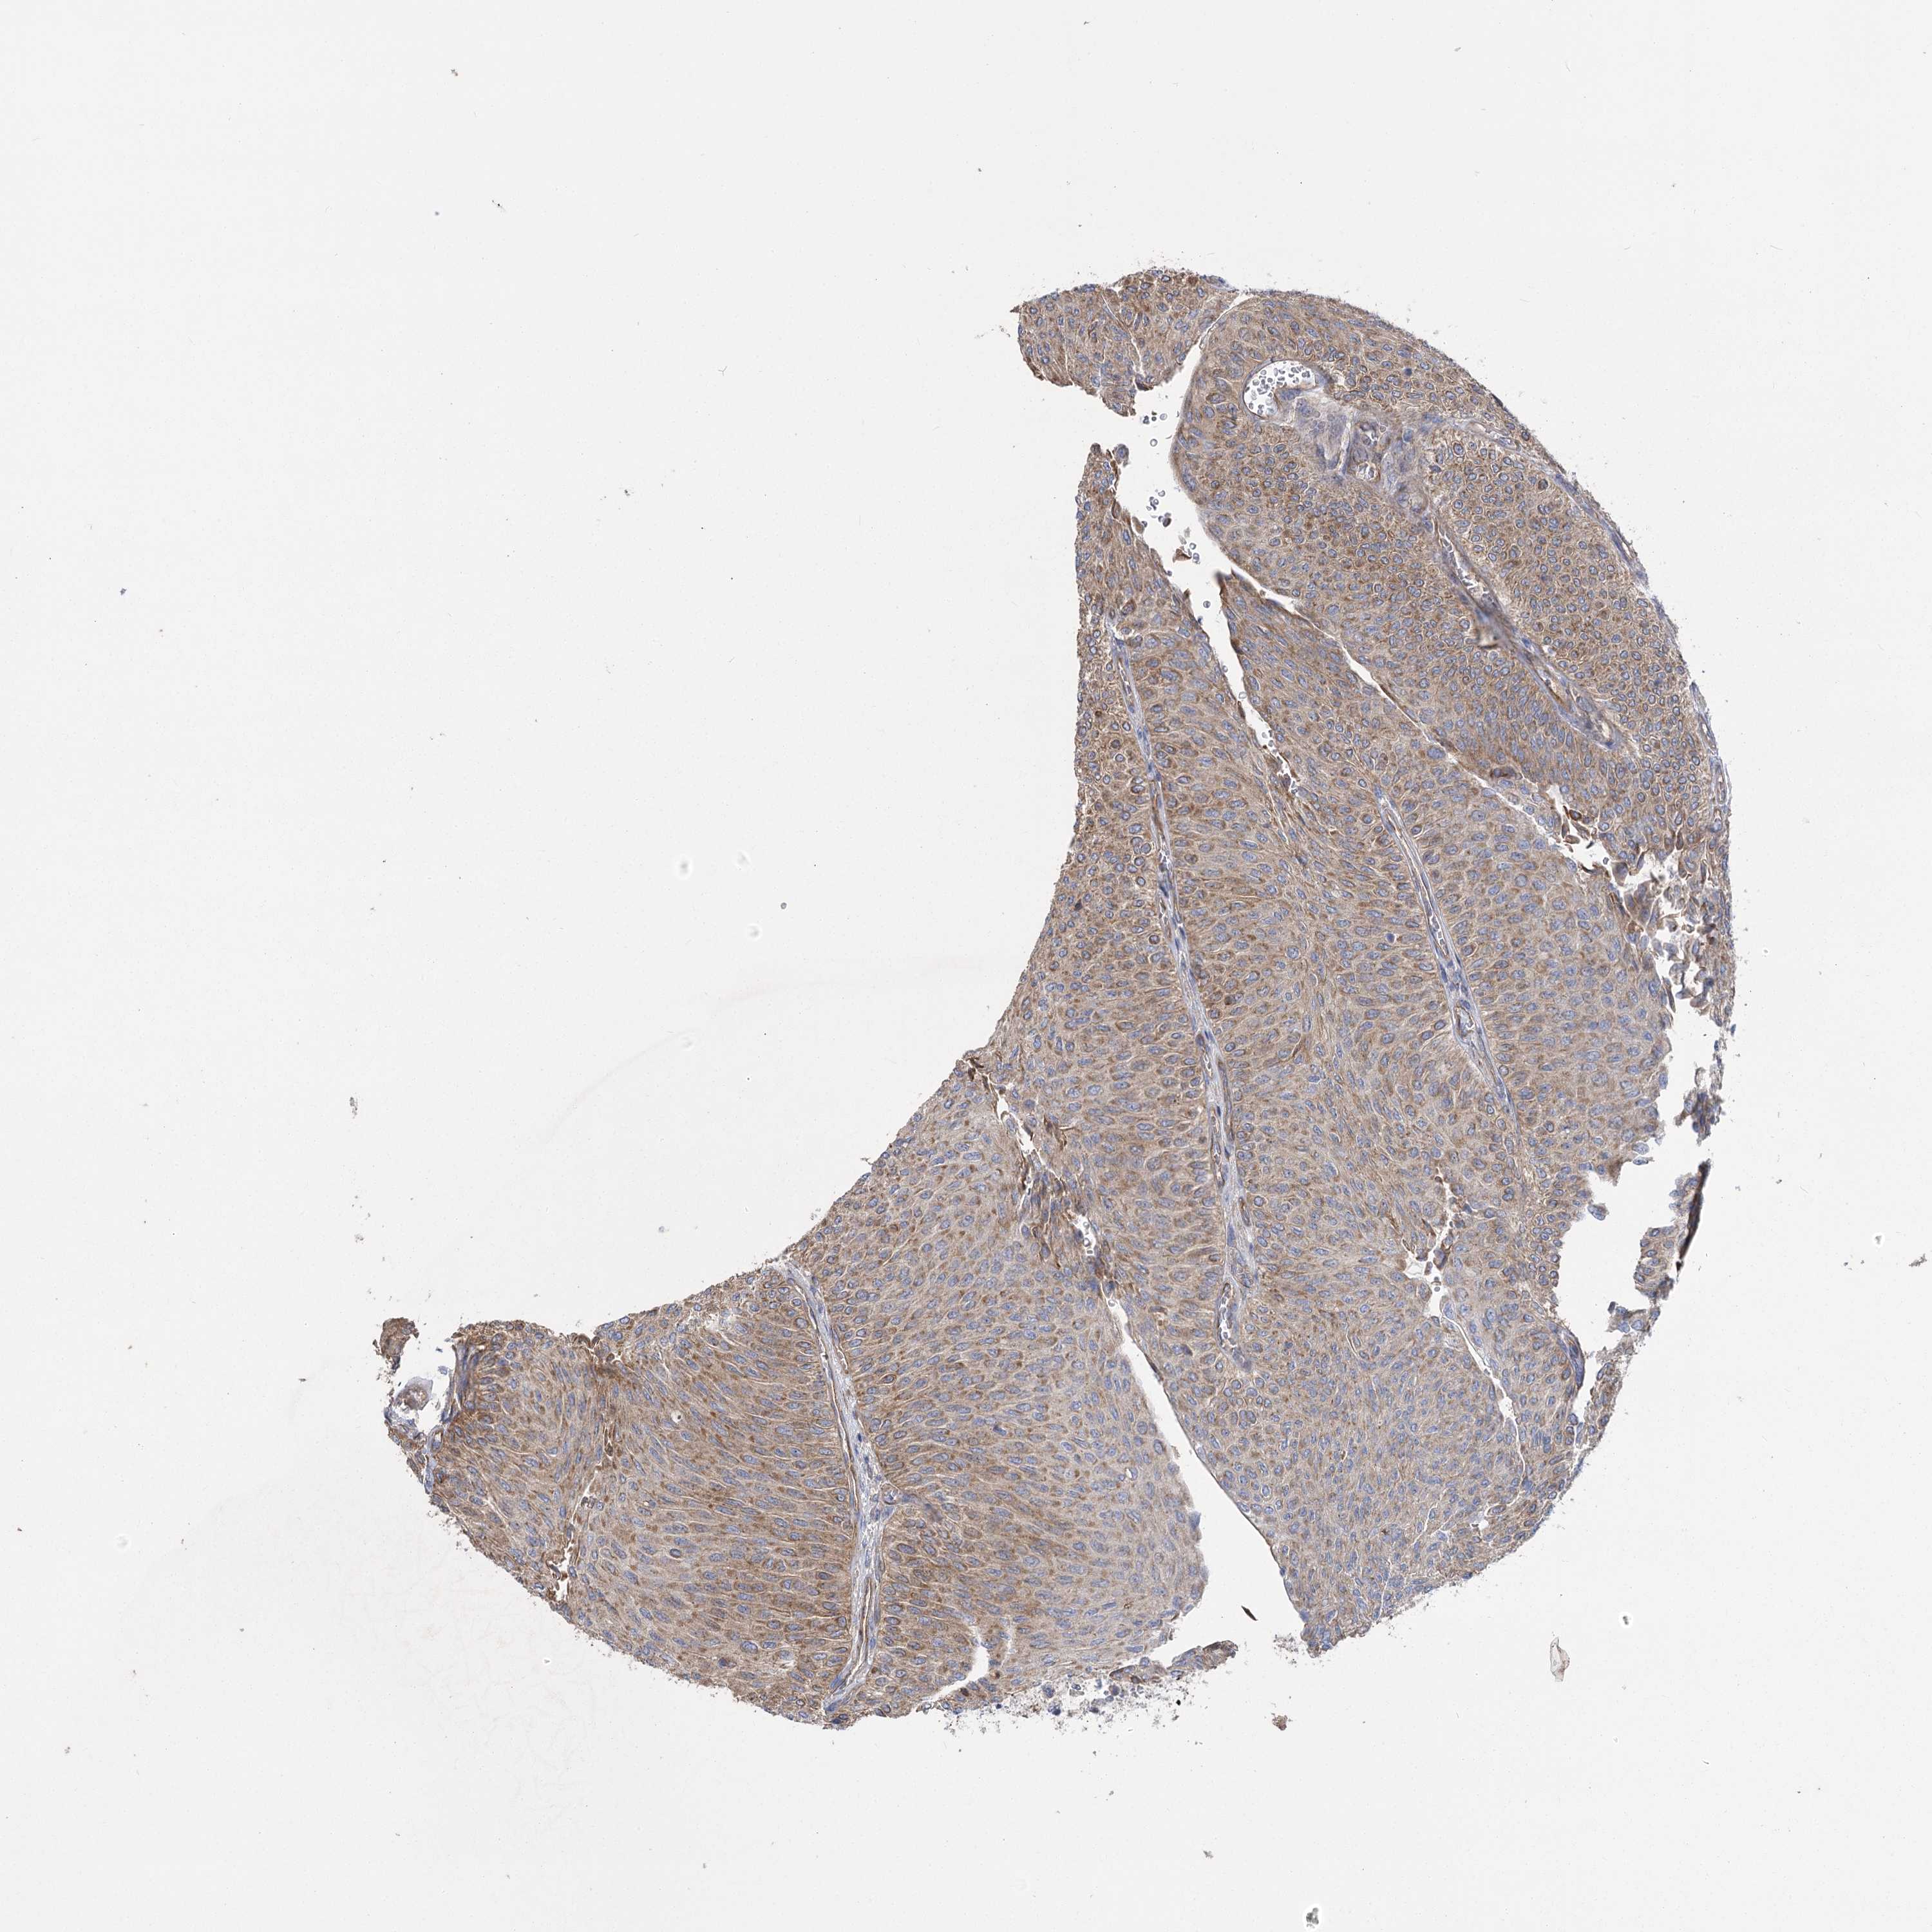

UROTHELIAL CANCER - Protein expressioni

A mouse-over function shows sample information and annotation data. Click on an image to view it in a full screen mode. Samples can be filtered based on level of antibody staining by selecting one or several of the following categories: high, medium, low and not detected. The assay and annotation is described here.

Note that samples used for immunohistochemistry by the Human Protein Atlas do not correspond to samples in the TCGA dataset.

Antibody stainingi

Antibody staining in the annotated cell types in the current human tissue is reported as not detected, low, medium, or high, based on conventional immunohistochemistry profiling in selected tissues. This score is based on the combination of the staining intensity and fraction of stained cells.

Each image is clickable and will lead to virtual microscopy that enables deeper exploration of all samples and also displays staining intensity scores, fraction scores and subcellular localization as well as patient and tissue information for each sample.

Antibody HPA034705

Antibody HPA034706

Staining

High

Medium

Low

Not detected

Intensity

Strong

Moderate

Weak

Negative

Quantity

>75%

75%-25%

<25%

None

Location

Nuclear

Cytoplasmic/membranous

Cytoplasmic/membranous,nuclear

Urothelial carcinoma, High grade

Urothelial carcinoma, Low grade

Urothelial carcinoma, NOS